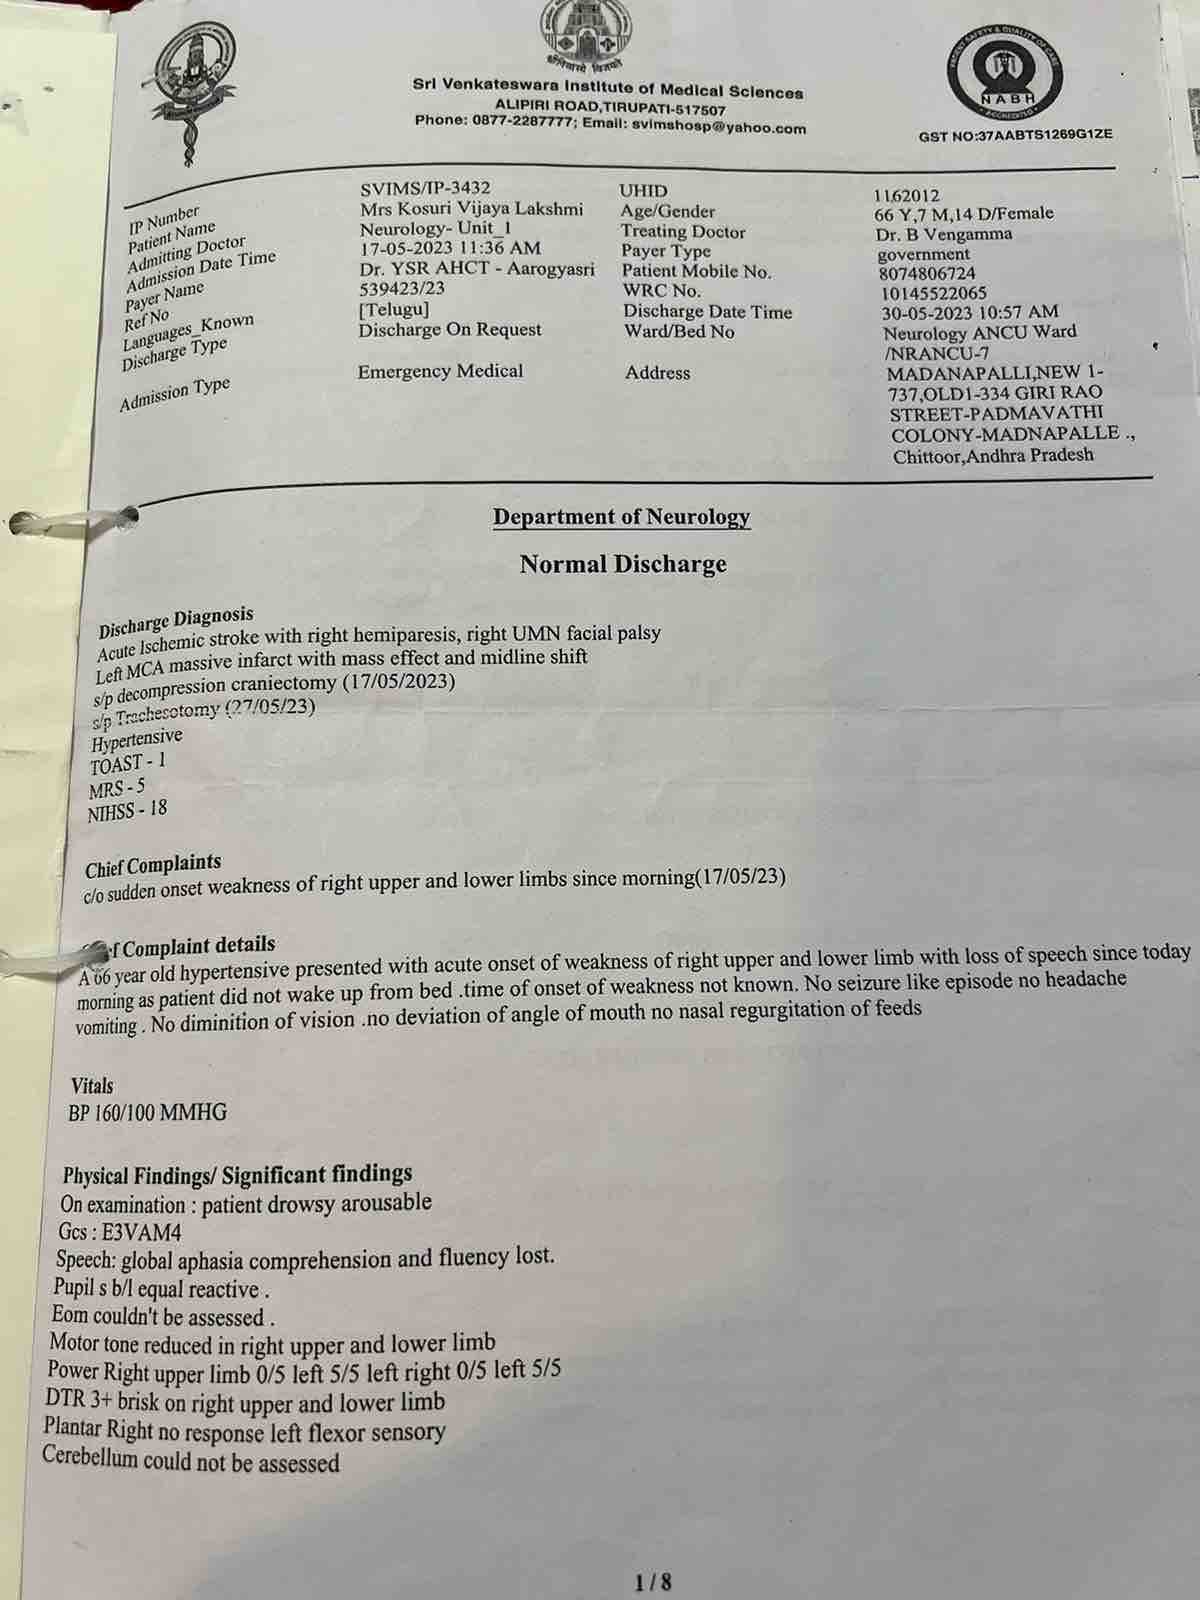

We are reaching out to you today with a heavy heart and a plea for help. Our beloved 66-year-old mother K VIJYA LAKSHMI, has been facing an incredibly challenging journey since 16th May when she had brain stroke & underwent emergency brain and abdomen surgery. Her recovery has been a rollercoaster of ups and downs.

During her hospitalization, she endured multiple complications, including respiratory distress, recurrent severe infections, and even seizure-like activity. Through it all, she has shown immense strength and determination. Still she require three more surgeries to stand on the path of recovery.